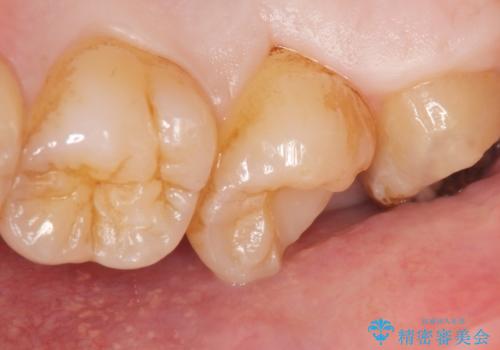

神経をとらずに済むよう丁寧にう蝕を除去したのち、セラミックインレーで修復しました。

自然な仕上がりと使用感にご満足頂けました。

詰め物の種類:セラミックインレー (e-max press)